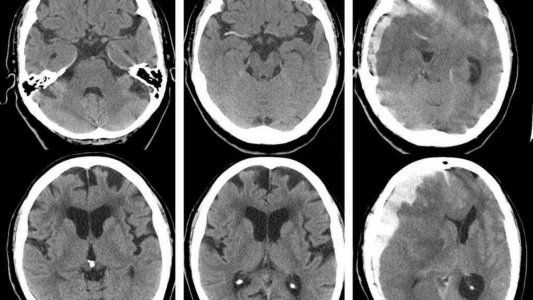

El hematomas subdural es una acumulación de sangre entre la cubierta del cerebro (duramadre) y la superficie del cerebro.

Un hematoma subdural es a menudo el resultado de un traumatismo craneal grave. Este tipo de hematoma subdural se encuentra entre el más difíciles de todos los traumatismos craneales. El sangrado llena la zona cerebral rápidamente, comprimiendo el tejido cerebral. Esto a menudo ocasiona traumatismo craneal y puede llevar a la muerte.

Los hematomas subdurales también se pueden presentar después de un traumatismo craneal menor. La cantidad de sangrado es menor y ocurre más lentamente. Este tipo de hematoma subdural a menudo se observa en adultos mayores. Pueden pasar desapercibidos por varios días a semanas y se denominan hematomas subdurales crónicos.

Con cualquier hematoma subdural, las pequeñas venas que están entre la superficie del cerebro y su cubierta externa (la duramadre) se estiran y se rompen, permitiendo que la sangre se acumule. En adultos mayores, las venas a menudo ya se han estirado debido al encogimiento cerebral (atrofia) y se lesionan más fácilmente.